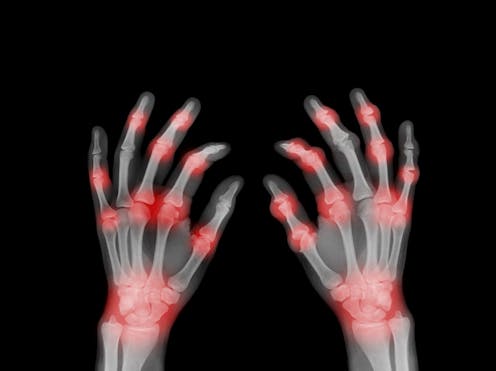

Rheumatoid arthritis affects 1 in 100 people worldwide. It causes inflamed, painful and swollen joints, often in the hands and wrists, and can lead to loss of joint function as well as chronic pain and joint deformities and damage. What causes this condition has been unknown.

Rheumatoid arthritis is an autoimmune condition, meaning it develops when the body’s immune system starts to attack itself. Proteins called antibodies, which usually help fight off viruses and bacteria, begin to attack the joints instead.